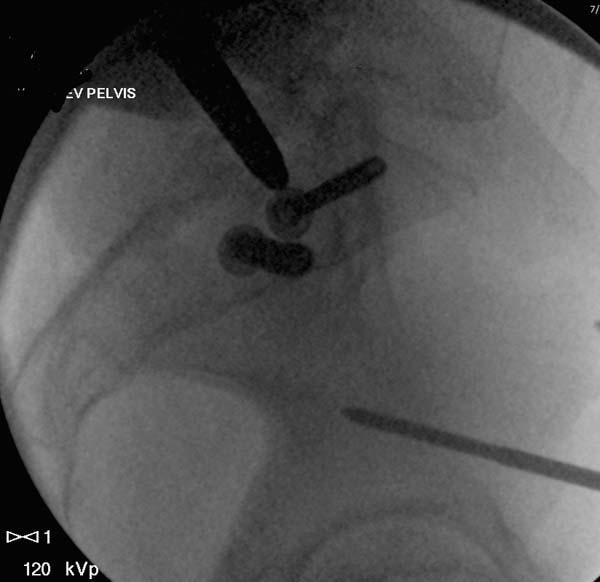

О преимуществах более стабильной фиксации,которая легко осуществляется

под рентгеном, говорили много раз. Слабость фиксации можно исправить за

счет нескольких стержней, проведенных более вертикально в подздошной

кости, или приближением стержней ближе к симфизу через AIIS.

Здесь снимки, которые показывают направление стержня, а также идею

репозиции вытяжением. На рентгенопроницаемых столах имеется возможность

установить дополнительную раму, где по желанию можно увеличить или

уменьшить высоту угла вытяжения. Для репозиции таза больной в положение

на спине, стержень для вытяжения остается во время операции. Система

подойдет для тракции головки бедра из вертлужной впадины, и для этого

стерильная веревка и Synthes Universal Chuck with T-Handle.

Двухстороннее повреждение крестца и травматическая ампутация бедра, где

неопытной бригадой дежурантов установлен верхний наружный фиксатор для

стабилизации. На третий день ревизия на более стабильный, и

окончательная фиксация. Первые снимки после стабилизации таза, и другие,

где показаны (параллельные) правильная установка на AIIS т.е на месте

прикрепления прямой мышцы бедра. Ампутация закончена костно пластическим

методом.